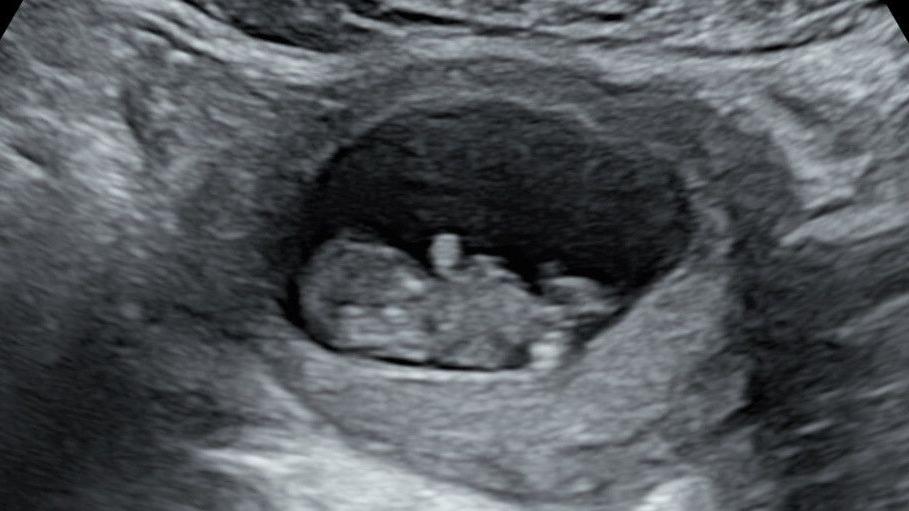

Um ultrassom fetal com imagem em preto e branco

Arquivo pessoal/Rhiannon Lawson

Um ultrassom do segundo bebê de Rhiannon Lawson, que foi diagnosticado com doença rara com 20 semanas